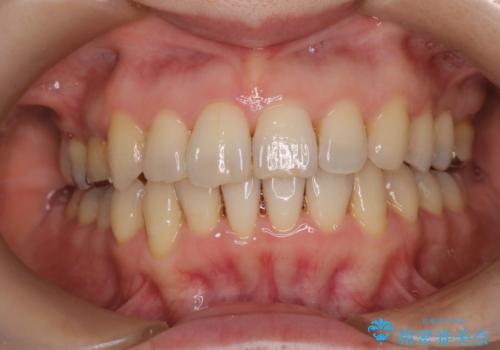

前歯の突出を防ぎながらガタつきを解消。上下左右4番抜歯による審美ワイヤー矯正

担当医 河口智英